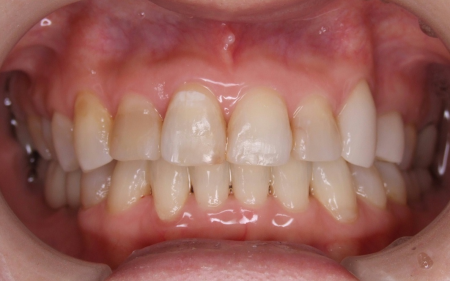

拝見したところ、歯と歯が並ぶ土台の骨「歯槽基底」の大きさの不調和により歯並びがガタガタになる「叢生(そうせい)」が全体的に生じており、また上下の前歯の重なりが深いため下の歯が見えない「過蓋咬合(かがいこうごう)」も認められました。

さらに左上の歯(第1小臼歯)の欠損部位は両隣の歯2本(犬歯/3番、第2小臼歯)を土台に人工歯を橋渡しにする被せ物「ブリッジ」が装着されており、お口を開けたときに銀歯が目立つことに加えて、歯の色が全体的に黄ばんでいるため見た目が良くない状態でした。

インプラントを埋め込んだことで食べ物がしっかり噛めるようになりました。歯の黄ばみも改善し、歯並びも整ったことで美しい口元を取り戻しています。